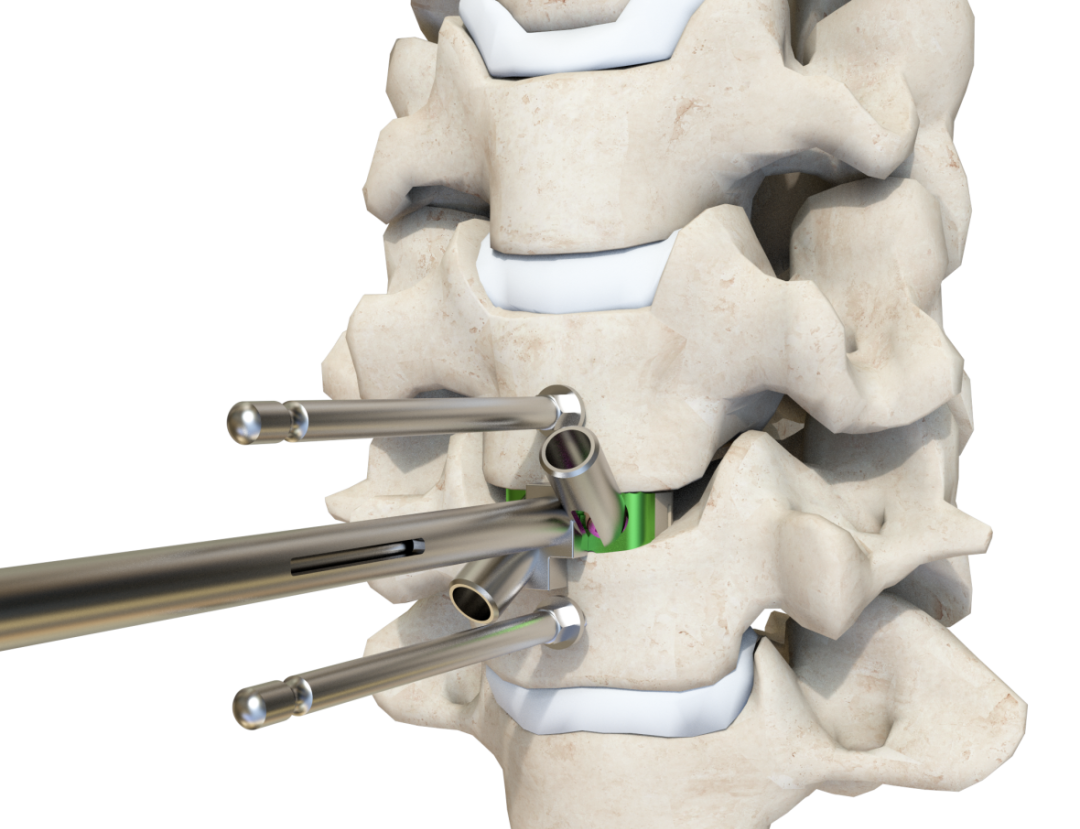

簡單的植入方式,縮短手術時間

3.適配工具